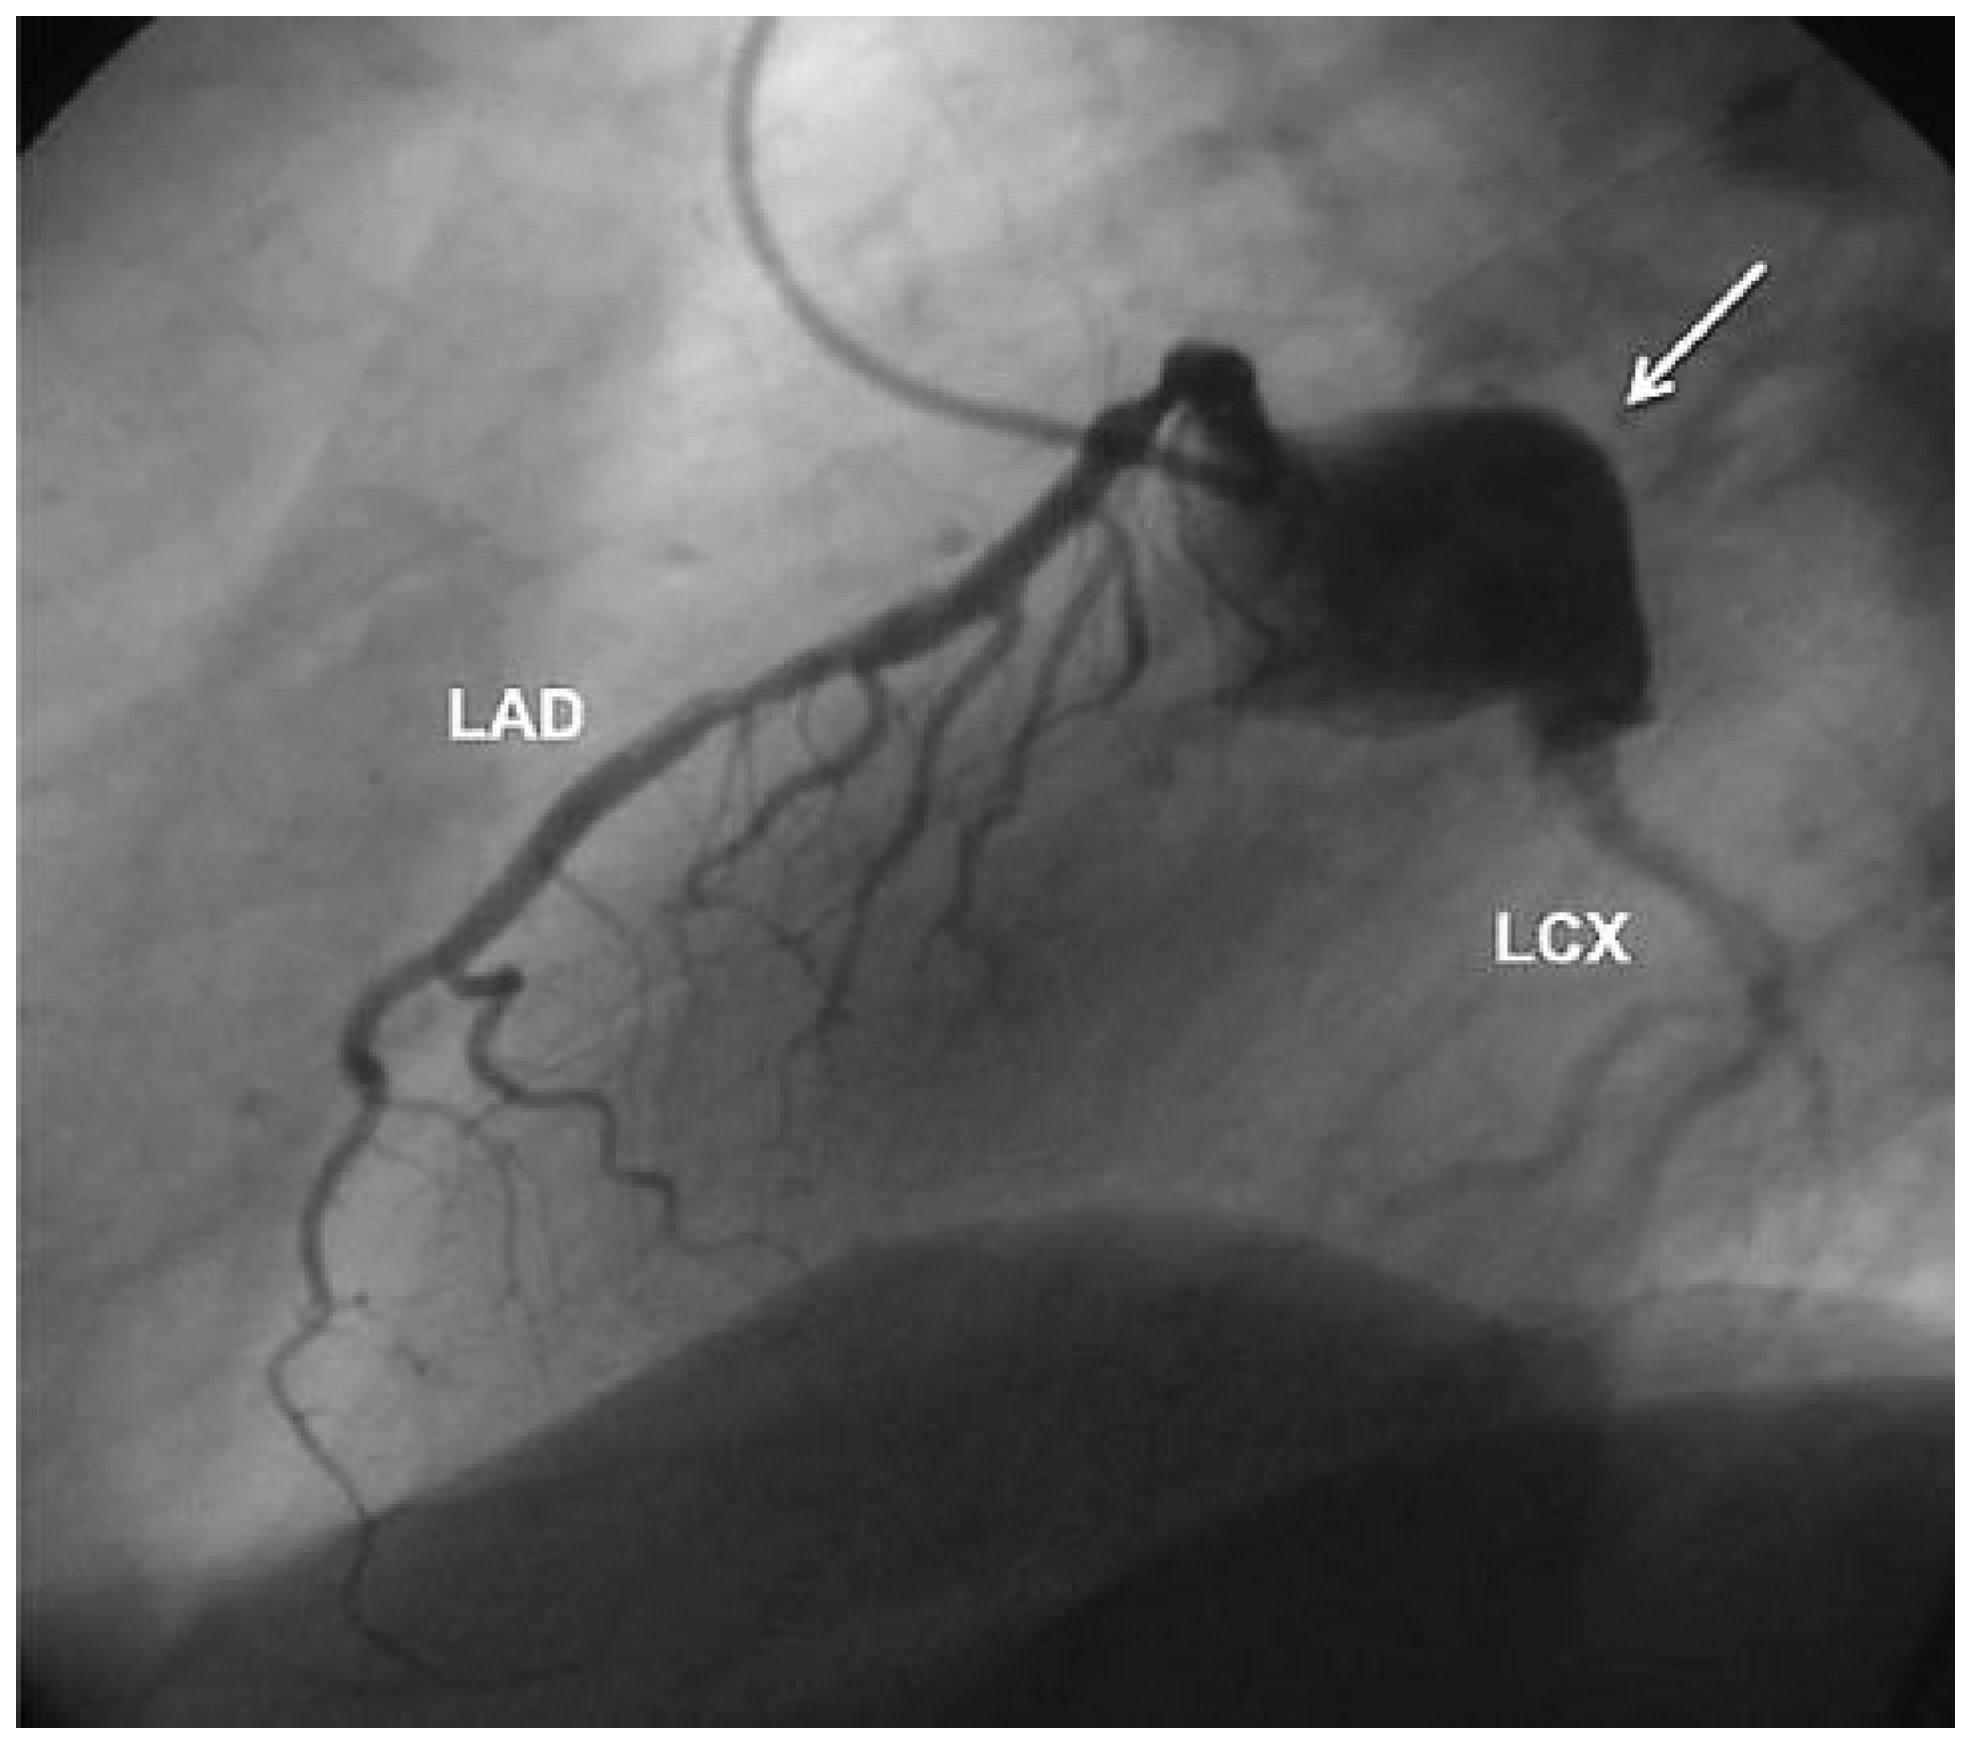

Aneurysm of the Left Circumflex Coronary Artery